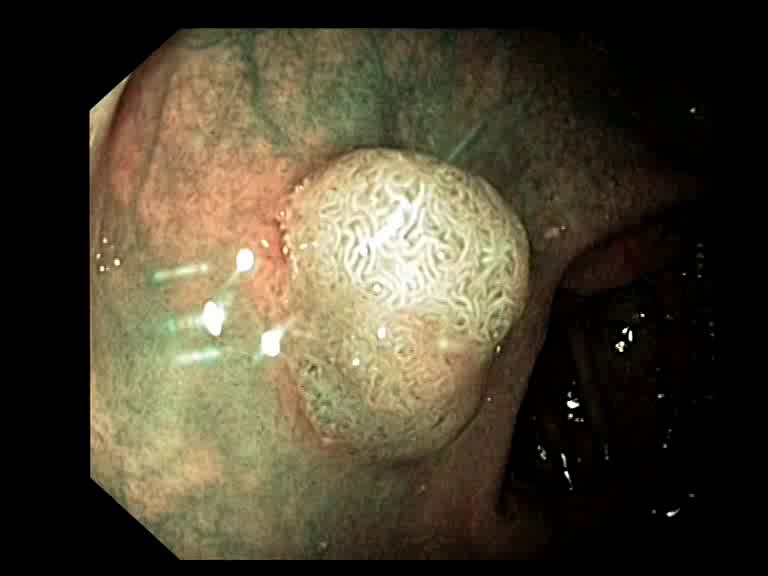

Figure 3: Key-frames obtained by our method and their corresponding depth maps. The polyp is visible from different viewing angles in these selected frames.

The selected key-frames are finally used to reconstruct the 3D surface of the polyp. We have used Facebook’s 3D image GUI to view the reconstructed polyp surface, the link to the video is shown here: https://youtu.be/PJKfk0Mqu2I\href https://youtu.be/PJKfk0Mqu2I. 3D visualization of a polyp helps in surgeries involving the removal of the polyp from its root. This gives better visualization of polyps for diagnosis. Fig. 3 shows some of the results of key-frame extraction and the corresponding depth maps. No publicly available datasets or methods using them that predict depth maps from endoscopic frames exist. Thus, a comparison between different methods for predicting depth from endoscopic images couldn’t be performed.